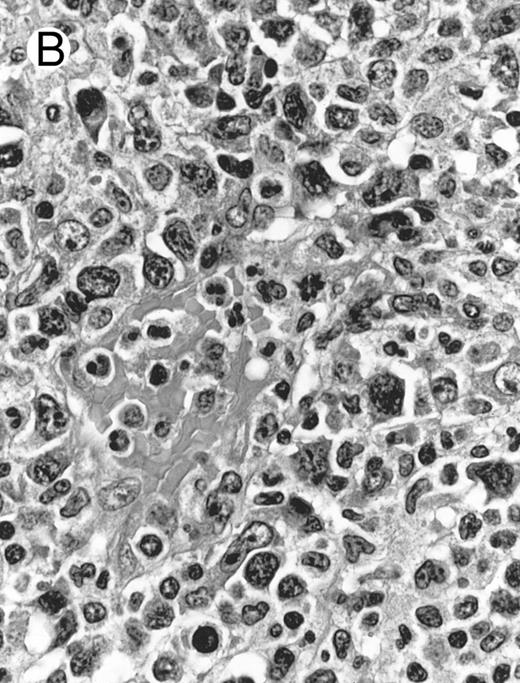

Histologically, the lymphomatous infiltrate was diffuse or patchy, with angiocentric and angiodestructive growth being observed in 30 cases (88.2%) (Figs 1 and 2). The cytologic composition was variable from case to case, including predominance of small cells, medium-sized cells, or large cells, or a mixture of these cell types (Fig 2 and 3). The tumor cell nuclei frequently showed irregular foldings and granular chromatin (Fig 2B). The larger cells possessed distinct nucleoli. The cytoplasm was moderate in amount and often pale. Karyorrhexis was usually prominent. Zonal tumor cell death, focal or confluent, was evident in 27 cases. In the 14 cases for which Giemsa-stained touch preparations were available, azurophilic granules could be identified in at least some of the neoplastic cells.

Fig. 2.

Laryngeal nasal-type NK/T-cell lymphoma relapsing as perforation of the terminal ileum (case no. 33). (A) The small bowel mucosa shows extensive necrosis and ulceration in the right field. There is also transmural lymphomatous infiltration. Note the vascular occlusion by lymphoma (arrow). (B) Higher magnification shows large and medium-sized lymphoma cells with irregular nuclear contours. The chromatin is fairly dense.